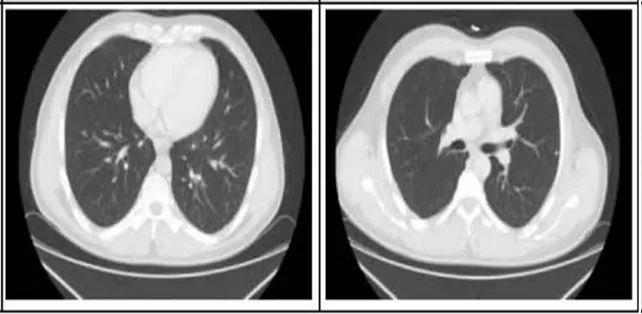

2. 肺部病灶治疗前后核磁对比:

肺部转移病灶在用药后2个月明显缩小,4个月后病灶基本消失。

治疗前

治疗2个月

治疗4个月